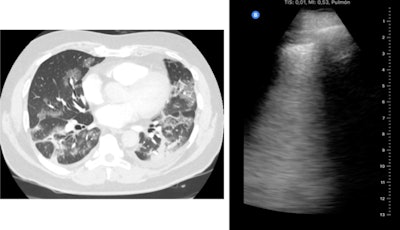

Chen conducted point-of-care ultrasound scans on all patients using a 12-zone protocol. Each zone was assigned a lung ultrasound score (LUS), with higher scores indicating more severe disease.

Out of the 51 patients in the study, 37 patients had findings suggestive of COVID-19 on CT and 40 had COVID-19-like findings on ultrasound. Statistical analysis revealed significant agreement between lung ultrasound and CT findings, including an ultrasound sensitivity of 100%, specificity of 79%, and positive predictive value of 93%.

Patients' lung ultrasound scores also had good correlation with their CT severity scores. Both LUS and CT scores were strongly correlated with patients' oxygen saturation, respiratory rate, and inflammatory markers, although the relationship was stronger for ultrasound.